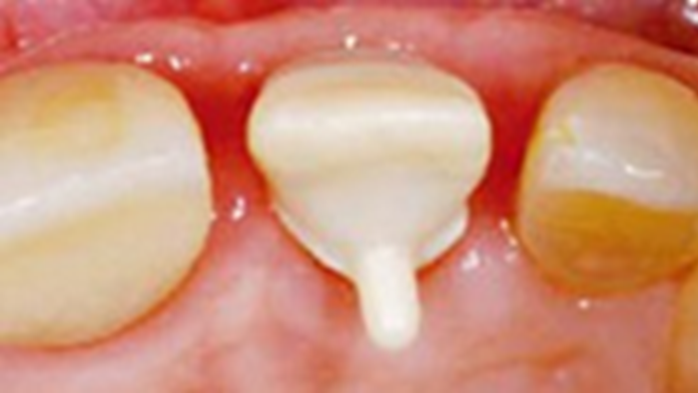

Clinical case: Immediate post-extraction insertion of implant & immediate loading

- Courtesy of Prof. Giuseppe Luongo, Italy -

AnyRidge, immediate loading, single implant, multicenter study, maxillary anterior, Prof. Giuseppe Luongo, single replacement

AnyRidge implant system

Immediate functional loading of single implants: a multicenter study with 4 years of follow-up

/J Dent Res Dent Clin Dent Prospect 2018; 12(1):26-37 | doi: 10.15171/joddd.2018.005

https://www.ncbi.nlm.nih.gov/pubmed/29732018